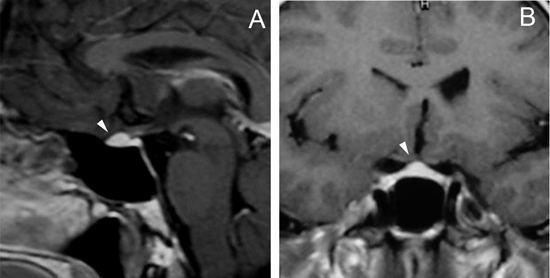

Figura 12A. Microadenoma pituitario (8 mm), corte coronal, secuencia convencional T1w con Gadolinio, el tumor lateralizado a derecha, erosiona y deforma el piso de la silla turca (punta de flecha). B. Mismo paciente, 3 meses post-tratamiento médico, corte coronal secuencia T1w con Gadolinio, El tumor ha modificado su forma, se ha reducido de tamaño (punta de flecha) y la glándula muestra ahora un borde superior cóncavo, con una pequeña herniación de la cisterna supraselar. Los macroadenomas pituitarios producen expansión de la silla turca, con moderado refuerzo del tumor después de la inyección de gadolinio. La densidad (TAC), intensidad de señal (RM) y características del refuerzo con medio de contraste yodado (TAC) o gadolinio (RM) no son específicas, pero el aumento de volumen y erosión de la silla turca, la invasión del seno cavernoso y la presencia de contornos lobulados (64%) son hallazgos frecuentes en un macroadenoma42-44. El aumento de volumen selar se observa en 94 a 100% y la erosión de las paredes de la silla turca, incluyendo el piso selar, dorso selar, tubérculo selar y extensión al seno esfenoidal, está presente en 76% de los macroadenomas. La invasión del hueso esfenoides y del clivus (Figura 2Ay 2B) se demuestra en 19% de los casos.

Figura 15 A, B y C. Cortes sagital T1w, coronal T1w Gad. y coronal T2w. Absceso pituitario que simula un macroadenoma quístico no funcionante.El compromiso del seno cavernoso (definido como la invasión perivascular de la arteria carotida interna), se observa en 19% de los macroadenomas y es habitualmente unilateral (Figuras 16A, 16B y 16C) pero puede ser bilateral en macroadenomas invasores (Figuras 17A y 17B). Para evaluar la invasión del seno cavernoso se utilizan las imágenes coronales T1w con gadolinio, efectuando el análisis de la forma y compartimientos del seno cavernoso y su relación con el adenoma; cuando el porcentaje de tumor que rodea la arteria carótida interna intracavernosa es mayor o igual a 66% del círculo medido alrededor de la carótida, hay invasión del seno, si es menor de 25%, el seno no está invadido48.

Figura 16A, B y C. Cortes coronales T1w sin y con Gadolinio y T2w. Macroadenoma con expansión asimétrica de la silla turca e invasión del seno cavernoso izquierdo.

Figura 17A y B. Cortes coronal y axial transversal, T1w Gad. Macroadenoma con crecimiento hacia lateral (entre puntas de flecha), mayor a derecha con invasión de ambos senos cavernosos; el quiasma está libre.Los adenomas invasores (Figuras 18 y 19) constituyen un grupo aparte y de acuerdo con series recientes publicadas representan entre 10% a 35% de los adenomas pituitarios operados49. En estos casos el potencial de invasión es estimado con mayor precisión con estudios histoquímicos y ultraestructurales de las muestras obtenidas durante la cirugía. Estos estudios patológicos, en conjunto con la cuantía de tumor residual demostrada con las neuroimágenes postoperatorias, definirán la conducta terapéutica a seguir.